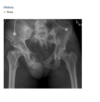

An anteroposterior view of the pelvis

(Fig. 2.24.1) in an elderly man shows extensive thick-

ening of the right iliopectineal line (arrows) with

coarsening of the trabecular pattern and increased

sclerosis throughout the entire right hemipelvis.

Paget disease (i.e., osteitis deformans)

disordered bone

remodeling affecting osteoblastic and osteoclastic

activity. Osseous involvement may be monostotic

or polyostotic, and 80% of the patients are asymp-

tomatic at the time of the discovery of the disease,

usually as an incidental finding on radiography or

because of elevated serum alkaline phosphatase and

elevated serum and urinary hydroxyproline.

stage I (acute phase), active and unbalanced osteo-

clastic bone resorption usually causes areas of lytic

bone destruction. In stage II (intermediate phase),

increased osteoblastic activity results in thickening of the cortex, coarsening of the trabecular pattern,

generalized bone overgrowth, and loss of corticome-

dullary differentiation. In stage III (late or inactive

phase), there is a diffuse increase in the density of

involved bone. Stage IV is the superimposed malig-

nant degeneration of Paget disease into a osteosarcoma.